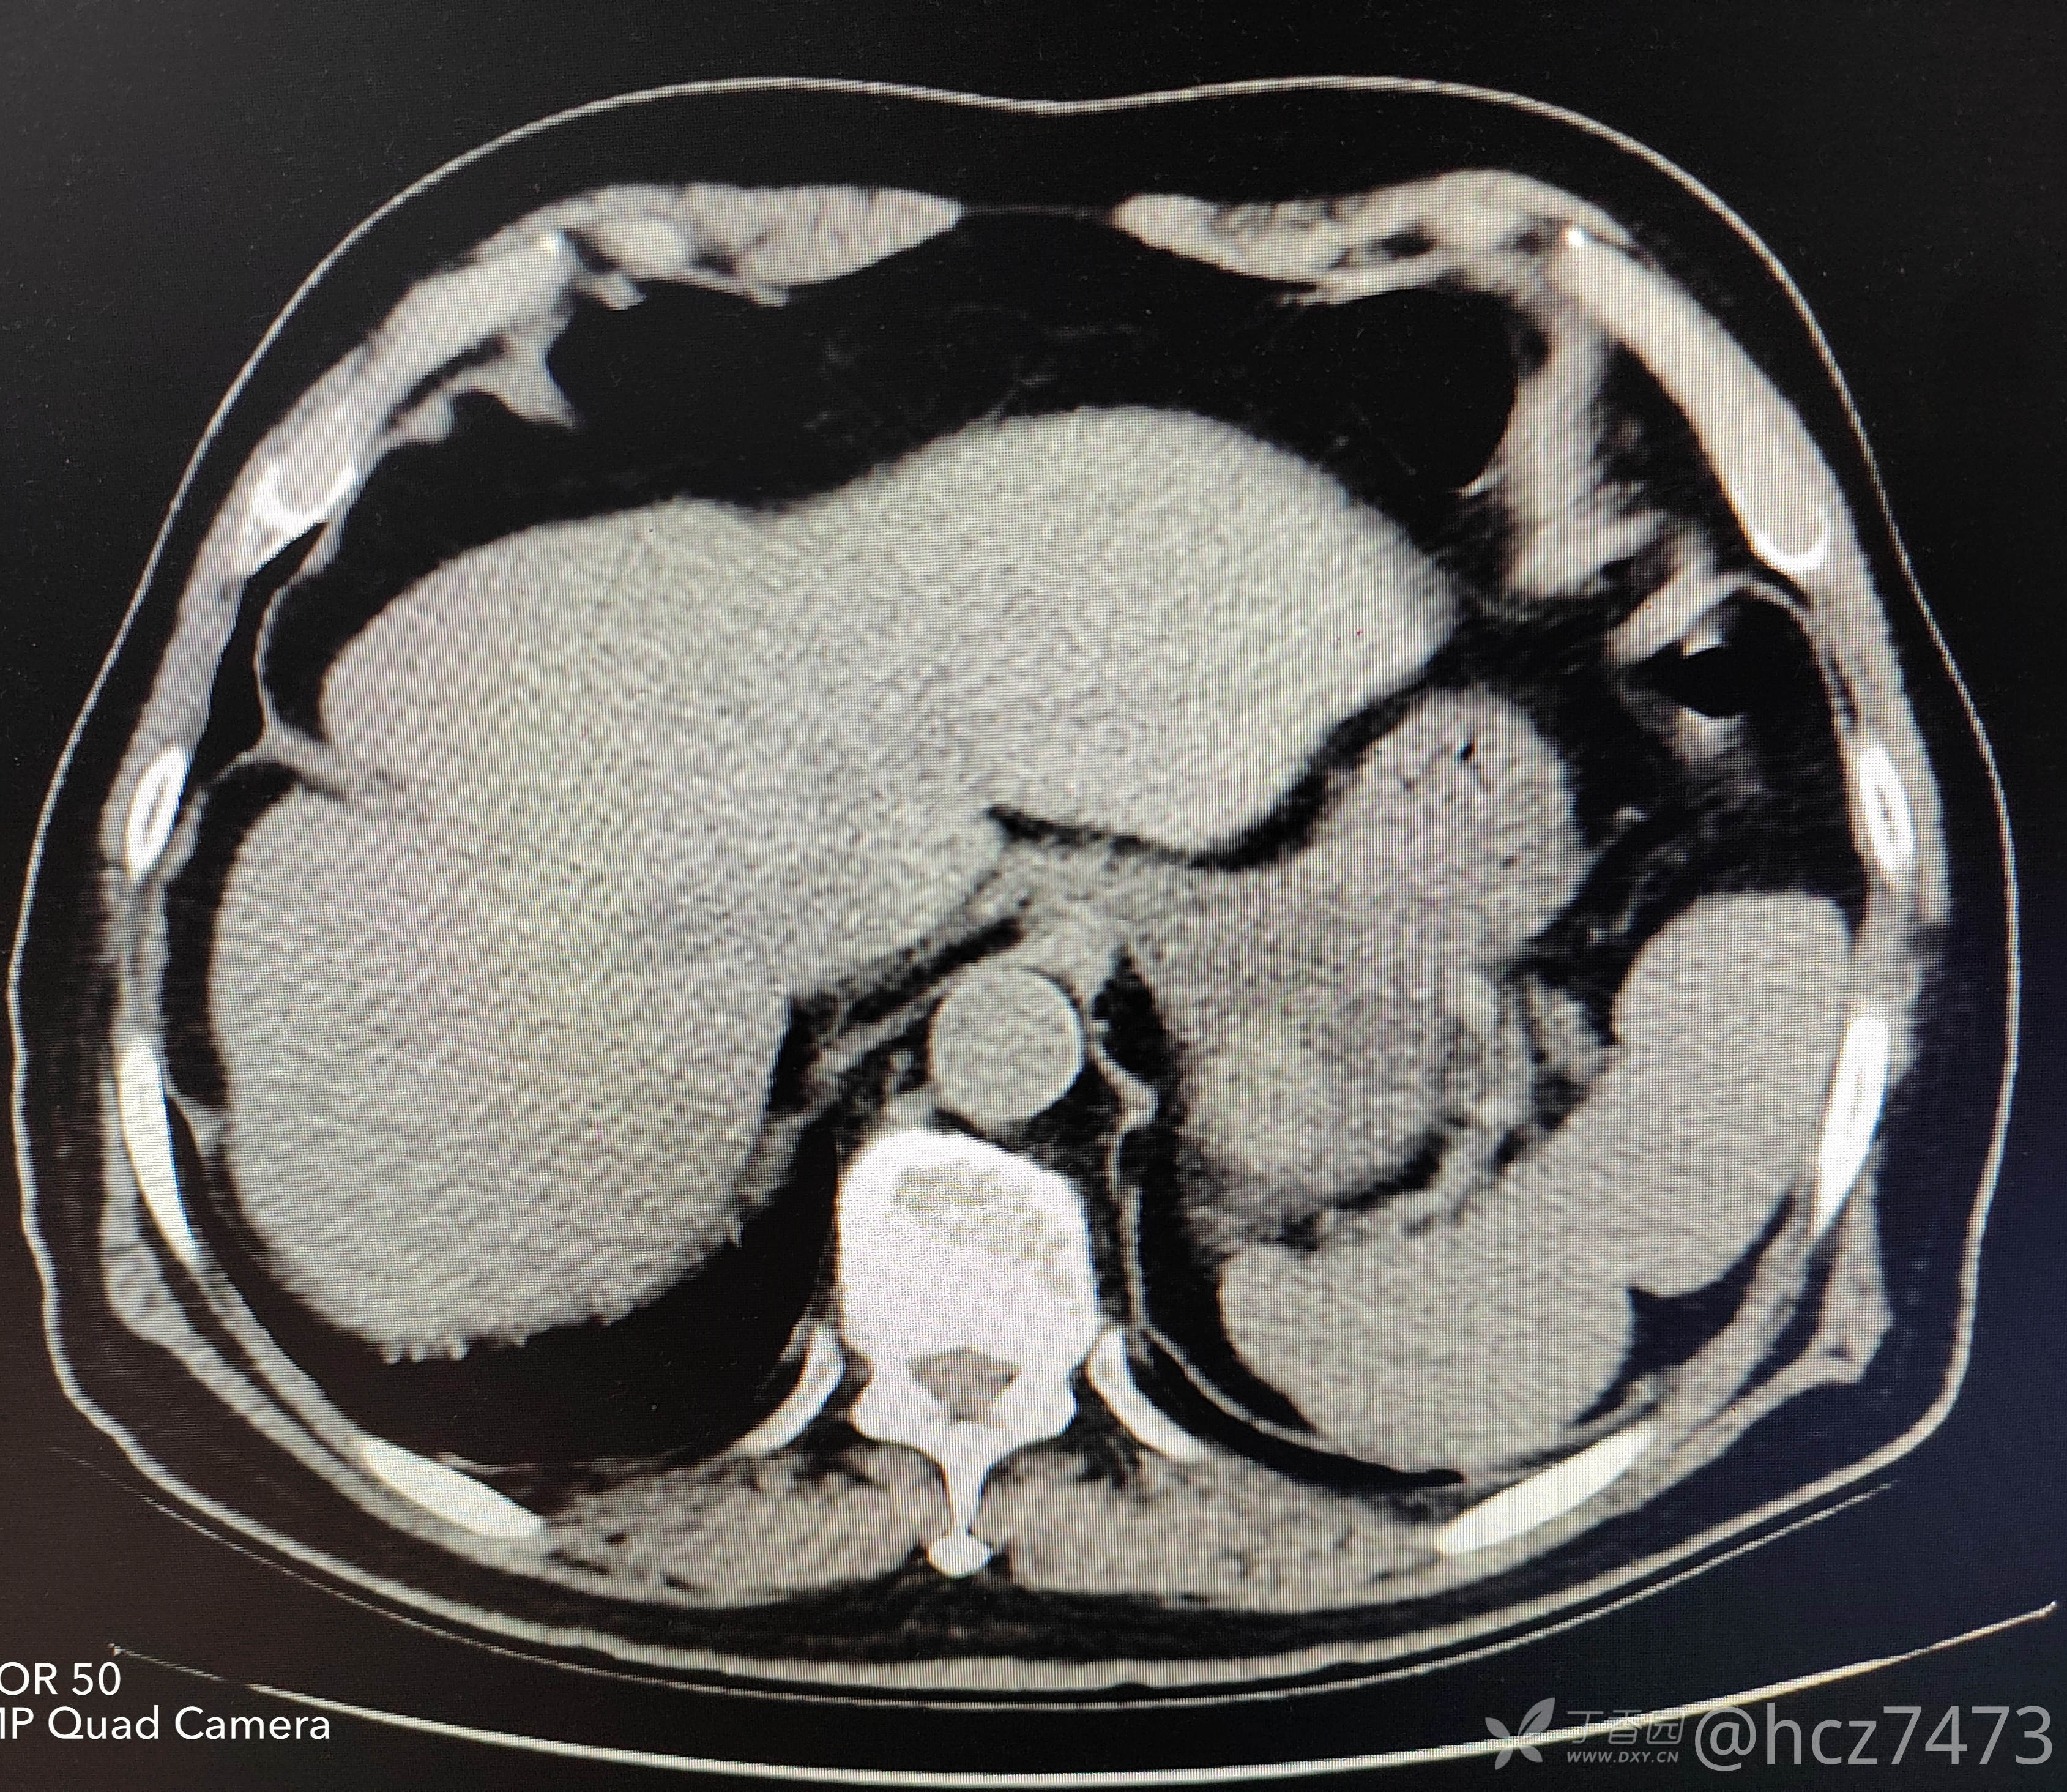

2022.05.12 我院腹盆腔CT检查:

CT报告:胃底部类圆形等密度影,肝左叶内低密度影,胰腺钙化灶,脾脏点状稍高密度影,左肾低密度影,膀胱后壁轻度增厚,前列腺增生。